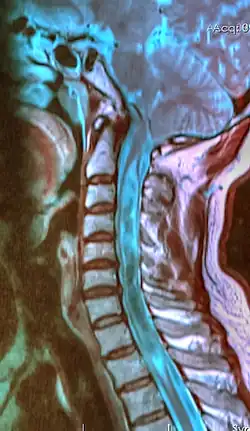

| A sagittal FLAIR MRI scan, from a patient with an Arnold–Chiari malformation, demonstrating tonsillar herniation of 7 mm. | |